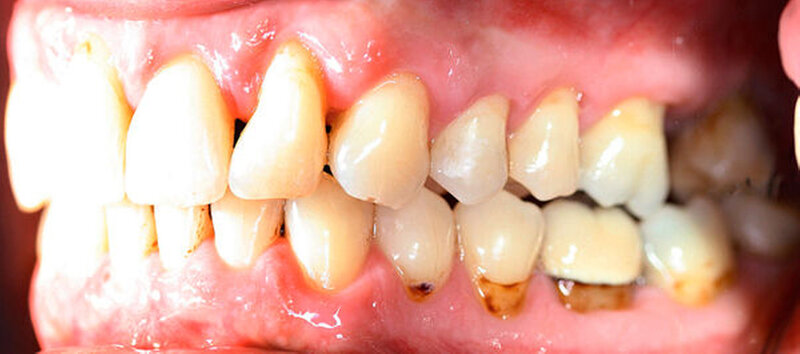

Anamnestisch lagen keine Besonderheiten vor. Es ist jedoch zu vermerken, dass ein regelmäßiger Alkohol-, Koffein- und Nikotinkonsum zugrunde lag. Intraoral zeigte sich ein bereits konservierend versorgtes permanentes Gebiss mit aktivem und inaktivem kariösen Geschehen. Große Anteile der Zahnhälse lagen nach Zahnfleischrückgang in Kombination mit Knocheneinbrüchen frei. Zahn 27 wurde bereits extrahiert.

Eine Beurteilung der parodontalen Situation an Zahn 11 offenbarte mesial und distal Sondierungstiefen von jeweils 6 mm.

Kieferorthopädisch imponierte beidseits eine neutrale Verzahnung bei einem tiefen Biss von 5 mm – bedingt durch die Verlängerung beider Frontzahngruppen. Besonders Zahn 11 zeigte eine erhebliche Verlängerung und Protrusion mit einer sagittalen Frontzahnstufe von 5 mm. Sowohl die Frontzähne im Ober- als auch im Unterkiefer wiesen eine lückige Beziehung zueinander auf (Abbildung 1).